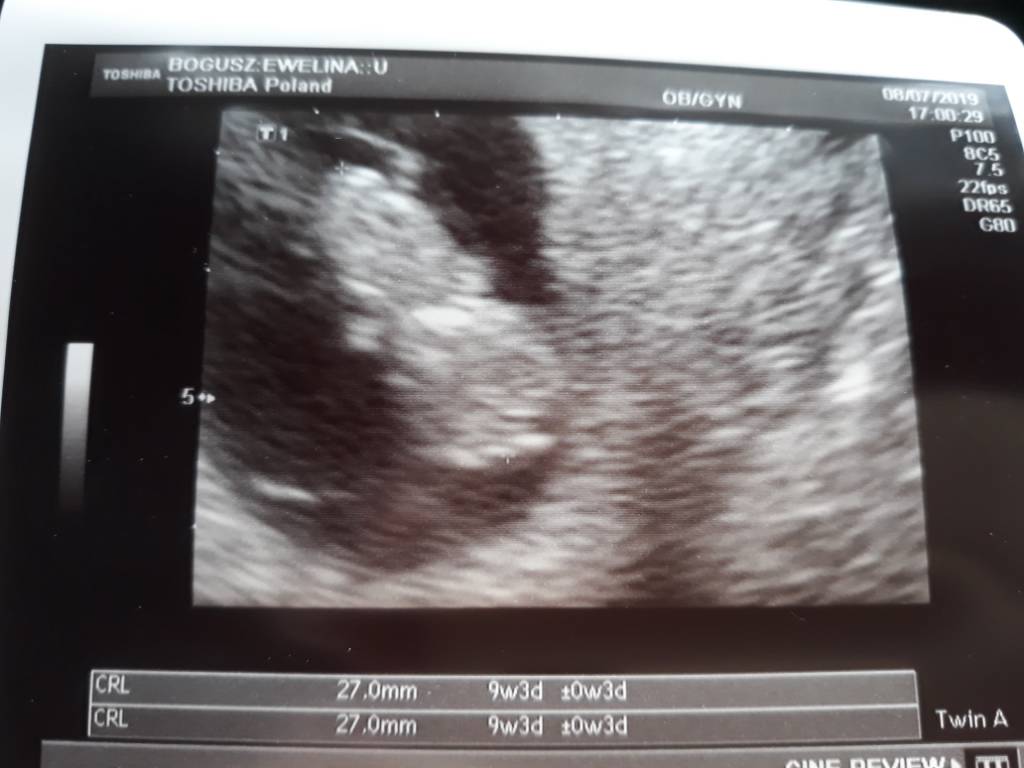

No bobas jak ta lala, i to kawał bobasa! To jak Ci dr zrobi ceaarke to się na porodówce nie spotkamyA oto mój dzieć. Dwie ręce, dwie nogi i głowa jest na miejscu. Wzrostu 2.7cm. Fikało koziołki już, nie mógł zdjęcia zrobić. Za dwa tygodnie mam mieć prenatalne, a za tydzień pappa u tego samego dr.

Gratuluje dużego szkrabaA oto mój dzieć. Dwie ręce, dwie nogi i głowa jest na miejscu. Wzrostu 2.7cm. Fikało koziołki już, nie mógł zdjęcia zrobić. Za dwa tygodnie mam mieć prenatalne, a za tydzień pappa u tego samego dr.